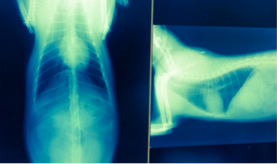

走った後の開口呼吸が目立つようになり検査をしたところ、エコー検査により生まれつき心臓の弁が長いことが発覚し、それによって心臓に負担がかかっているようです。そして、BNP(血液中の心臓バイオマーカー)の数値は、なんと基準値100以下に対して、1500オーバーで計測不能でした。

(※名前が旧姓となっております。)

肥大した心臓は元には戻らないのでやはり緩和治療しか治療法が無く、生涯投薬生活を送らなければならない病気です。急な心不全や血栓が詰まることによる突然死もあり得る怖い病気です。

肥大化した心臓のレントゲン